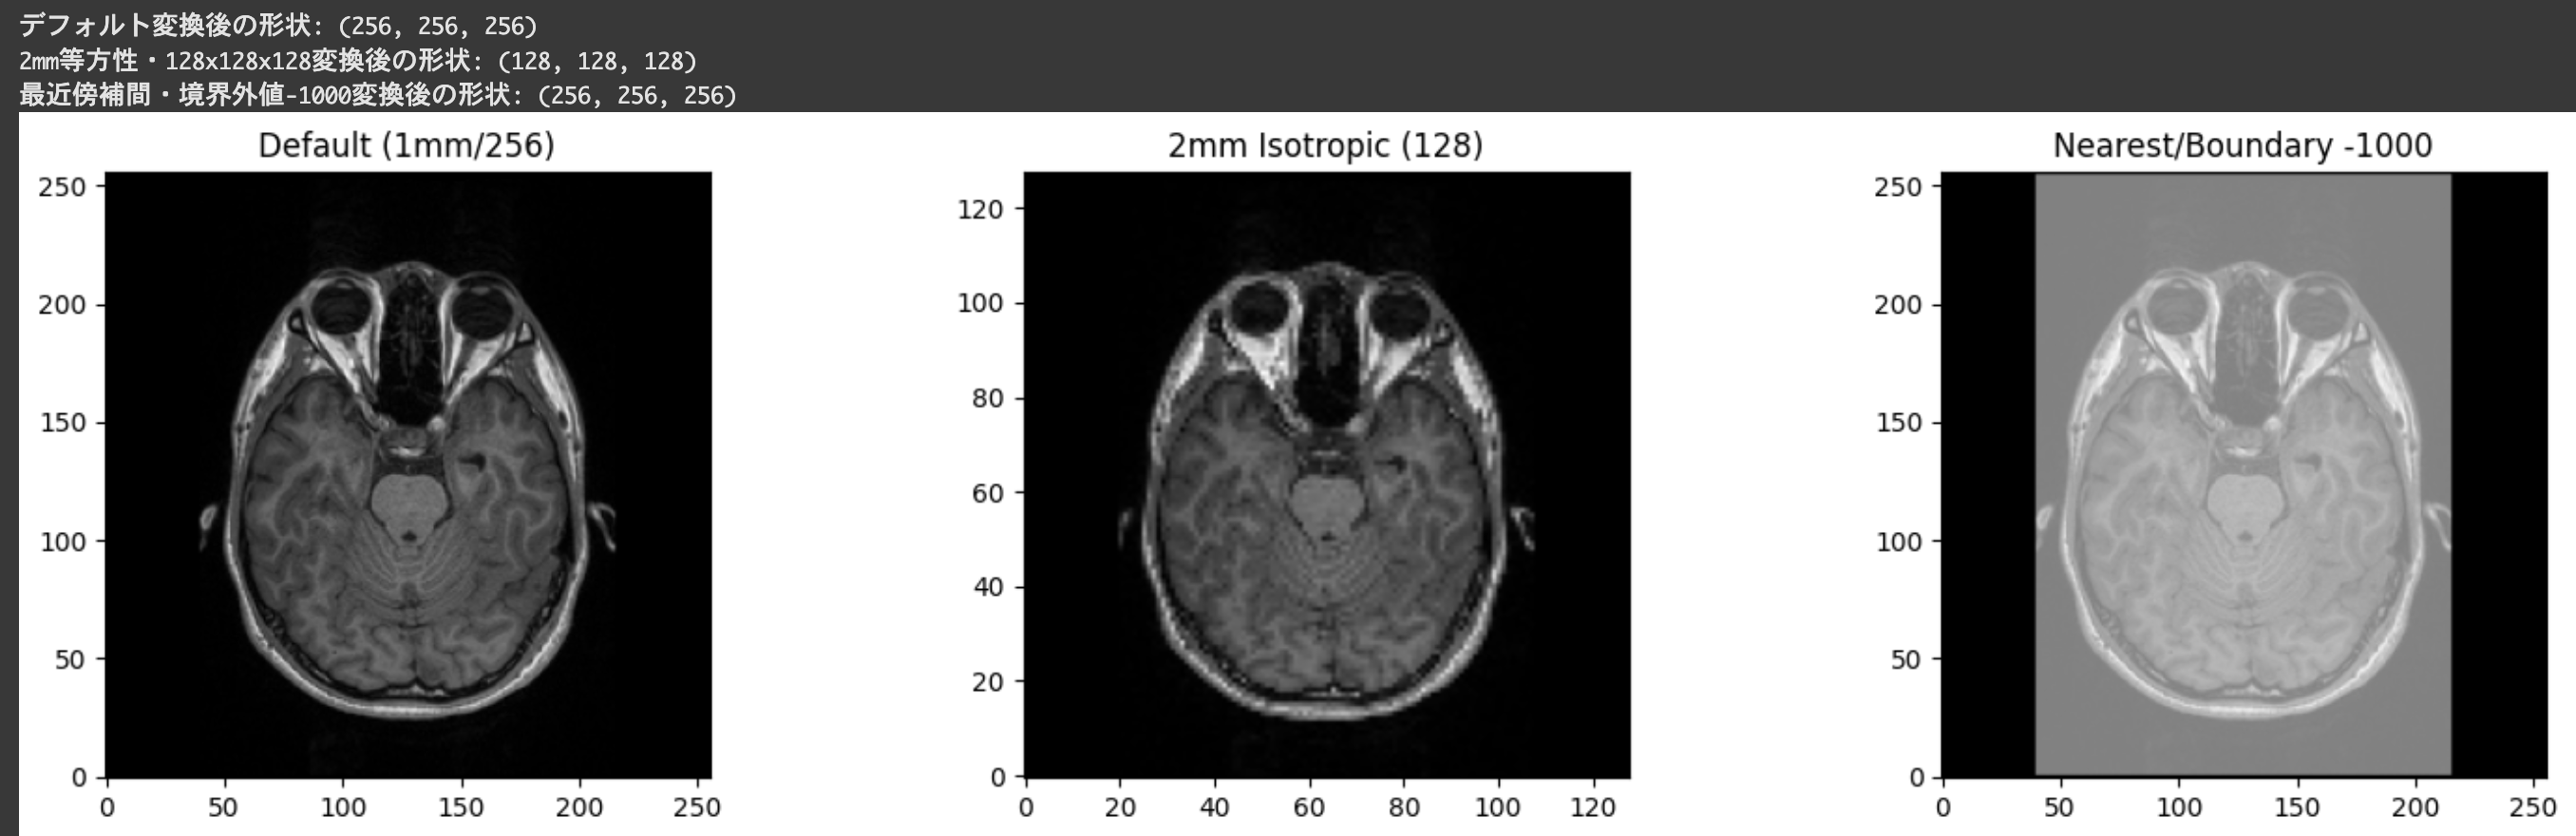

conform関数の詳細

conform関数は、MRI画像を標準的な形状とボクセルサイズに変換するための強力なツールです。conform関数は、引数で細かく指定しない場合、デフォルトで1mm等方性ボクセルサイズの256×256×256の3D画像に変換します。これにより、異なるスキャナーや撮像シーケンスから取得した画像を均一な形式に揃えることができます。

conform(from_img, out_shape=(256, 256, 256), voxel_size=(1.0, 1.0, 1.0), order=3, cval=0.0, orientation='RAS', out_class=None)主な引数:

- from_img:変換したい画像オブジェクト

- out_shape:出力画像の形状(デフォルト: (256, 256, 256))

- voxel_size:出力画像のボクセルサイズ(mm単位)(デフォルト: (1.0, 1.0, 1.0))

- order:スプライン補間の次数(デフォルト: 3)。0は最近傍補間、1は線形補間、3は3次スプライン補間(より滑らか)

- cval:境界外の値(デフォルト: 0.0)

- orientation:出力画像の向き(デフォルト: 'RAS')

conform関数は、さまざまな引数を組み合わせることで、用途に応じた柔軟な画像変換が可能です。

import matplotlib.pyplot as plt

# 例1: デフォルト設定(1mm等方性・256x256x256・3次スプライン補間)

img_conformed_default = processing.conform(img, voxel_size=(1.0, 1.0, 1.0))

print(f"デフォルト変換後の形状: {img_conformed_default.shape}")

# 例2: 2mm等方性ボクセル・形状(128,128,128)・線形補間

img_conformed_2mm = processing.conform(

img,

out_shape=(128, 128, 128),

voxel_size=(2.0, 2.0, 2.0),

order=1 # 線形補間

)

print(f"2mm等方性・128x128x128変換後の形状: {img_conformed_2mm.shape}")

# 例3: 1mm等方性・256x256x256・最近傍補間・境界外値を-1000に設定

img_conformed_axial = processing.conform(

out_shape=(256, 256, 256),

voxel_size=(1.0, 1.0, 1.0),

order=0, # 最近傍補間

cval=-1000.0 # 境界外値

print(f"最近傍補間・境界外値-1000変換後の形状: {img_conformed_axial.shape}")

# 画像の中央スライスを表示して変化を比較

def show_center_slice(img_obj, title):

data = img_obj.get_fdata()

center = tuple(s // 2 for s in data.shape)

# 軸位断面(z軸中央スライス)を表示

plt.imshow(data[:, :, center[2]].T, cmap='gray', origin='lower')

plt.title(title)

plt.figure(figsize=(15, 4))

plt.subplot(1, 3, 1)

show_center_slice(img_conformed_default, "Default (1mm/256)")

plt.subplot(1, 3, 2)

show_center_slice(img_conformed_2mm, "2mm Isotropic (128)")

plt.subplot(1, 3, 3)

show_center_slice(img_conformed_axial, "Nearest/Boundary -1000")

plt.tight_layout()

plt.show().png)